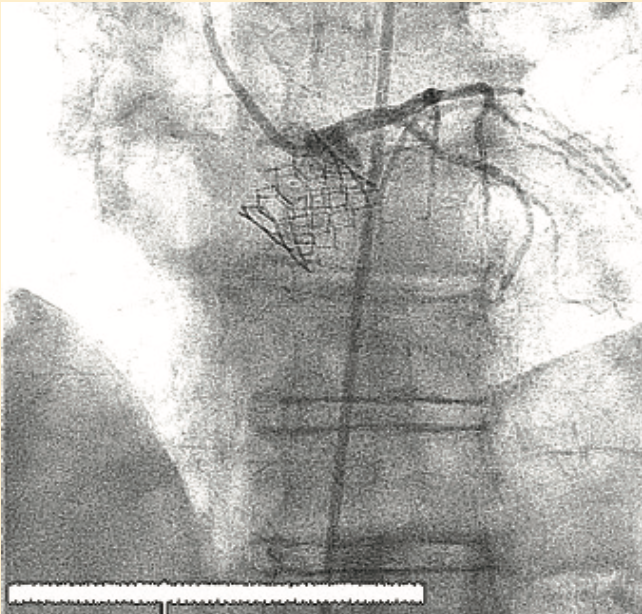

Her root anatomy was notable for low left coronary artery height (9.2 mm above the level of the aortic annulus [Figure 1]) and small aortic sinus measurements (23-25 mm in all dimensions). She was referred for transfemoral transcatheter aortic valve replacement (TF TAVR) utilizing the BASILICA (bioprosthetic aortic scallop intentional laceration to prevent iatrogenic coronary obstruction) technique to percutaneously lacerate the native left coronary cusp leaflet of the aortic valve prior to implantation of a 20 mm Sapien 3 transcatheter heart valve (Edwards Lifesciences).

We planned to use cerebral protection during the case upfront, but the patient was known to have anomalous origin of her bilateral carotid arteries off of a single branch from the aortic arch, separate from the right brachiocephalic, and an anomalous insertion of the brachicephalic to the distal arch (Figure 2). We performed an aortic arch angiogram using a 15 cc contrast injection through a 5 French (Fr) pigtail with the ACIST CVi system (ACIST Medical) (Figure 3, Video 1) to guide the cerebral protection device from the anomalous brachiocephalic to protect the carotids. We proceeded with laceration of the left coronary cusp aortic valve leaflet. Aortic root angiography was performed using the same 5 Fr pigtail and a 10 cc contrast injection (Figure 4), then coronary angiography to identify the left coronary cusp (Figure 5). The optimal alignment of the left coronary cusp was determined by using a 6 Fr Amplatz left (AL) 1 guide catheter and a 6 cc injection with a lower pressure injection (Figure 6, Video 2). Finally, after the laceration was completed and the valve deployed (using small test injections from the ACIST contrast injector) (Figure 7, Video 3), we performed peripheral angiography with the 5 Fr pigtail advanced from the contralateral iliac artery to ensure adequate hemostasis of the large 14 Fr sheath access site (Figure 8, Video 4).